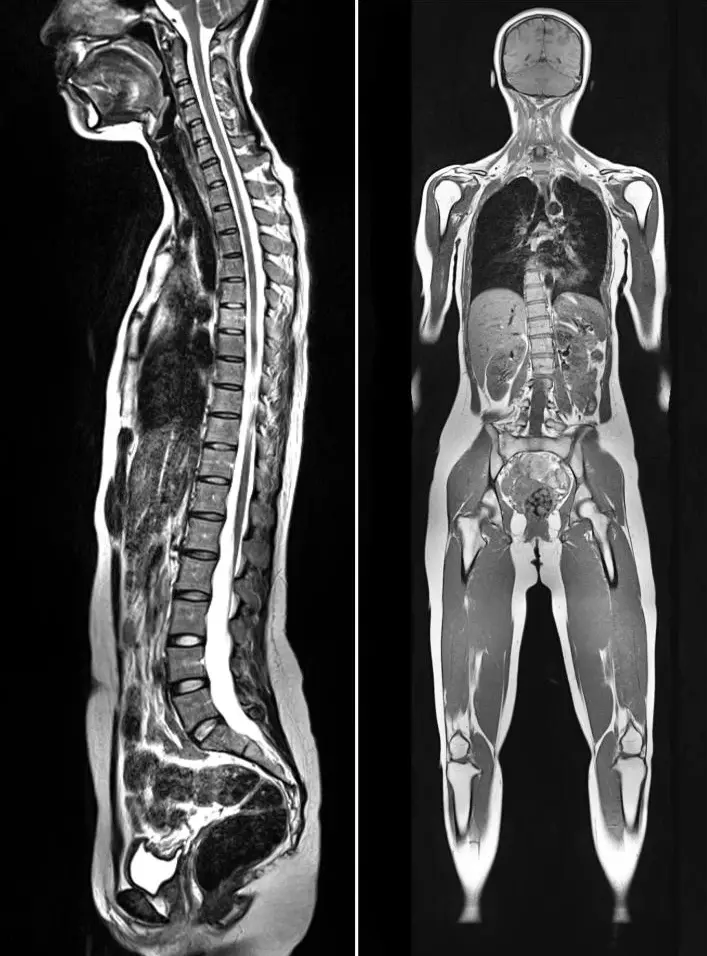

Our modern CT imaging delivers quick, accurate results while ensuring a calm, safe, and comfortable experience for every patient.

Our CT scan services deliver fast, accurate, and detailed cross-sectional images to help physicians diagnose and monitor a wide range of medical conditions. Using advanced low-dose CT technology, we ensure high-quality imaging while prioritizing patient comfort, safety, and confidence.

Computed tomography (CT) is an advanced imaging system that uses a combination of X-rays and computer technology to produce comprehensive images of specific areas of your body, including your bones, chest, head, joints, lungs, and spine. CT scans give a much more detailed picture than regular X-rays and can identify many conditions that may escape detection on other imaging tests, such as lung cancer.

Computed tomography (CT) is an advanced imaging system that uses a combination of X-rays and computer technology to produce comprehensive images of specific areas of your body, including your bones, chest, head, joints, lungs, and spine. CT scans give a much more detailed picture than regular X-rays and can identify many conditions that may escape detection on other imaging tests.

CT is often ordered when more detail is needed based on results of other studies, when the cause of symptoms is unclear during a physical exam or when an asymptomatic patient has increased risk of certain disease. CT scans can be performed on any part of the body. Low-dose studies are used to screen for certain diseases, such as lung cancer, colon cancer, and heart disease.